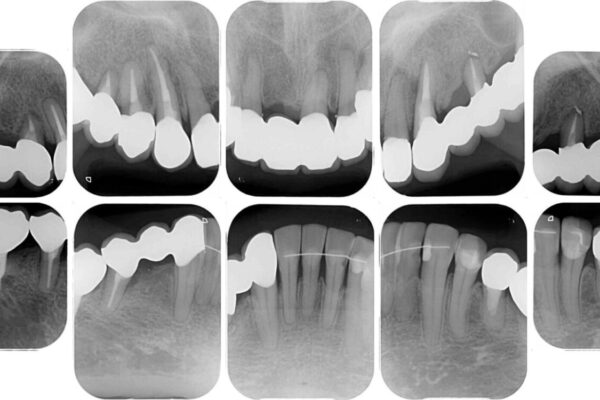

治療前

• 放置したインプラントとインビザライン 全顎リカバリー治療 治療前画像